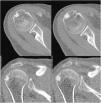

Caso clínico 1Mujer de 49 años, que consulta por un dolor de hombro derecho (miembro dominante) de 10 días de evolución, con un dolor más intenso en decúbito supino. El dolor no ha cedido con antiinflamatorios no esteroideos. En la exploración física, la paciente presenta un balance articular completo con dolor en la movilidad activa, sobre todo en la abducción por encima de 80°. Las maniobras de Jobe y Hawkins son positivas. En la radiografía simple se observa una calcificación entre la cabeza del húmero y el acromion (fig. 1), y ante la sospecha clínica de tendinitis calcificante de hombro, se solicita una RM (fig. 1).

Radiografía simple de hombro, proyección anteroposterior: se observa una calcificación entre la cabeza del húmero y el acromion (imagen superior izquierda). Imágenes de RM: se observa una calcificación del supraespinoso con una lesión osteolítica en la tuberosidad mayor de aproximadamente 1cm de diámetro y un importante edema óseo de la cabeza humeral de 36×39mm (imágenes superior derecha, inferior derecha e inferior izquierda).